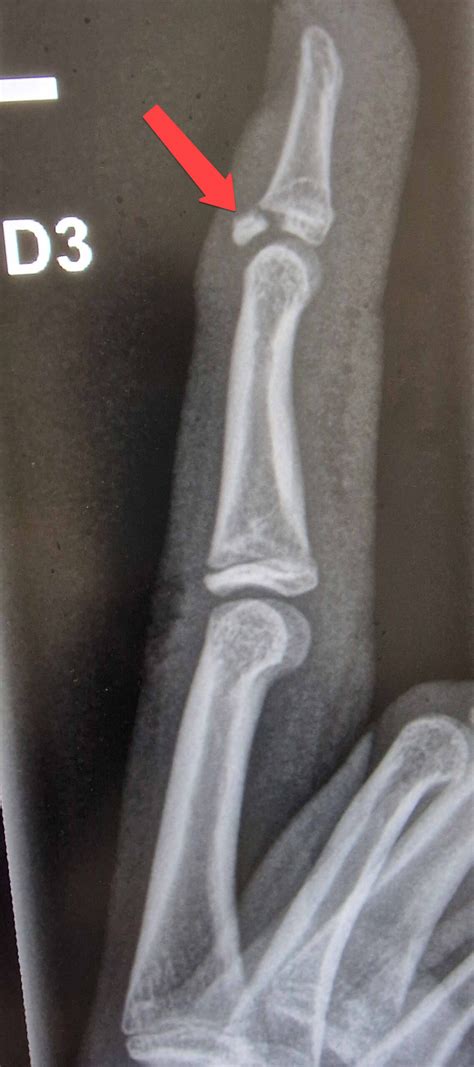

• X-rays: The primary method to identify bone fragments or gaps in the bone structure.